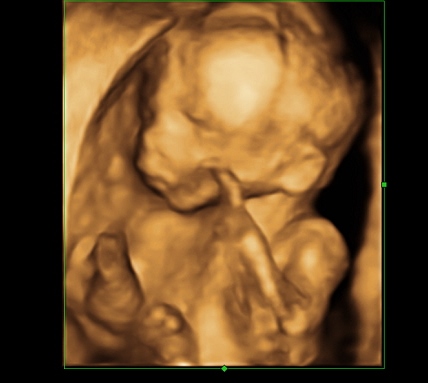

I have a great update this week because I just got back from my 20 week ultrasound and appointment with the doctor. Everything is looking great and the doctor has no concerns at all. I go back again in 4 weeks but until then I just get to enjoy feeling little one's movements. They should get stronger in weeks to come so yay for that. My DH has felt it once but since then when he puts his hands on my belly LO stops. LOL being a brat already. My bump has appeared and those who know me have said oh there is your baby bump. I've attached some pictures so please enjoy. The ultrasound tech was nice enough to switch it to 3d for the last few shots and I've attached the best one. Ahh still can't believe this is happening. I even told the doctor I keep waiting for something to happen and he said well everything looks great and will continue that way. Stupid IF brain.